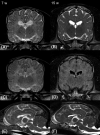

FIGURE 3

Follow‐up brain MRI at 15 weeks of age. The figure displays MRI of the brain from the affected dog 3 at 7 and 15 weeks of age. The upper row shows T2W transverse images at the level of the interthalamic adhesion (A, B), the middle row shows corresponding transverse FLAIR images (C, D), and the lower row shows T2W midsagittal images (E, F). Subcortical white matter appears hyperintense to gray matter at 7 weeks and isointense at 15 weeks of age on T2W and FLAIR images. Thus the affected dog failed to display the normal transition phase to white matter hypointensity, which occurs in healthy Beagles at 6 weeks (T2W) and 8 to 36 weeks of age (FLAIR). 26 FLAIR sequence failed in this dog at 7 weeks of age presumably due to artifact (C). 30 FLAIR, fluid attenuation inversion recovery; MRI, magnetic resonance imaging